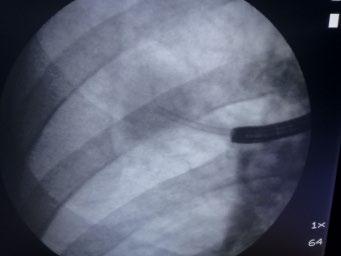

lesions extended further into the bronchial wall, even into the adjacent tissue and small lymph nodes that evaded diagnosis by computed tomography (CT) [38]. When by EBUS exploration only strictly localized tumors were treated by PDT, in all patients long-lasting complete remission was achieved [39]. Thus it was proven that it was not failure of the PDT, as had been assumed, but of local staging of these lesions. Which means that supposedly early lesions should be explored by the described methods, before a decision on the method of endoscopic treatment is made. Thus in a more extensive localized lesion, if surgery is not considered, endobronchial brachytherapy might be preferable because of its deeper penetration (Figure 1.10).

1.10 Early lung cancer. The slight discoloration on white light becomes very prominent by autofluorescence (a). By magnifying endoscopy, the pathological vascularization becomes visible (b), which is even more prominent under NBI (c). In the EBUS image, the superficial lesion ventrally is thickened (3 mm) compared to the normal wall on the left (1.4 mm), but well within the confines of the bronchiall wall and can be treated by bronchoscopic intervention (d).